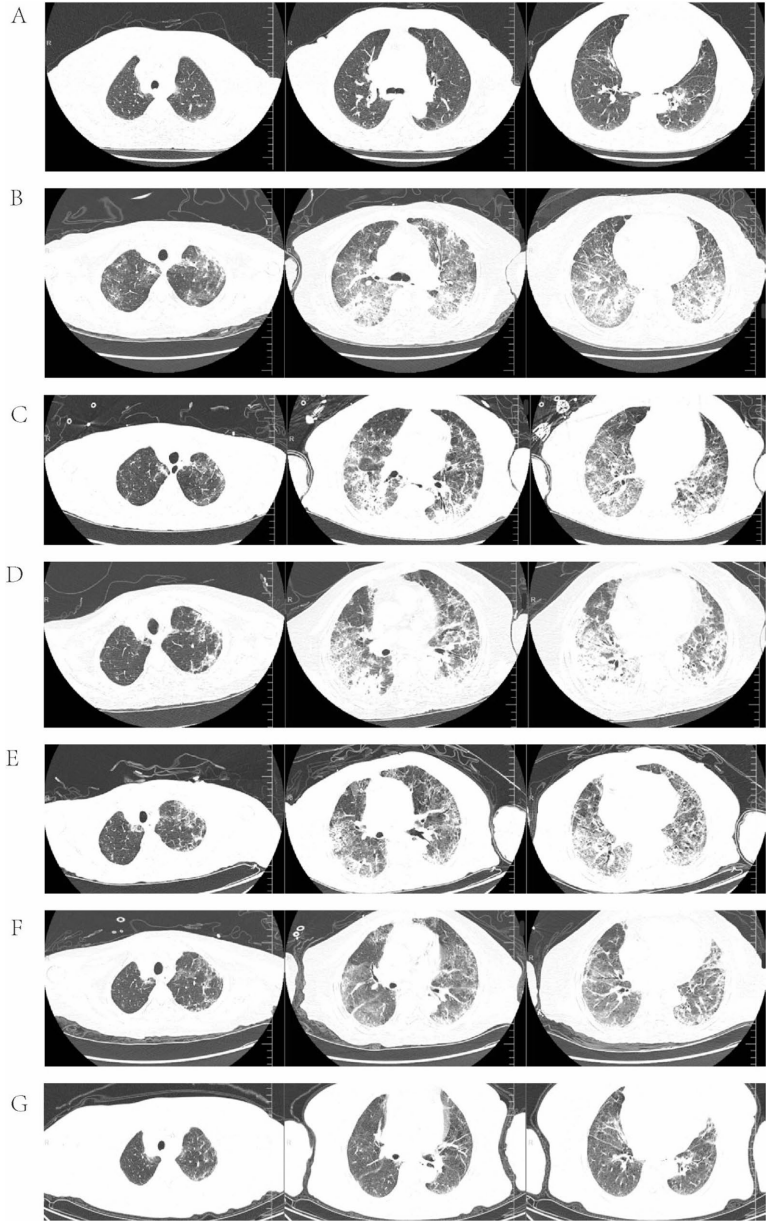

当激素减量导致病情反复时(

),采用80mg甲基强的松龙联合静脉免疫球蛋白的强化方案,最终实现肺部病变显著吸收(